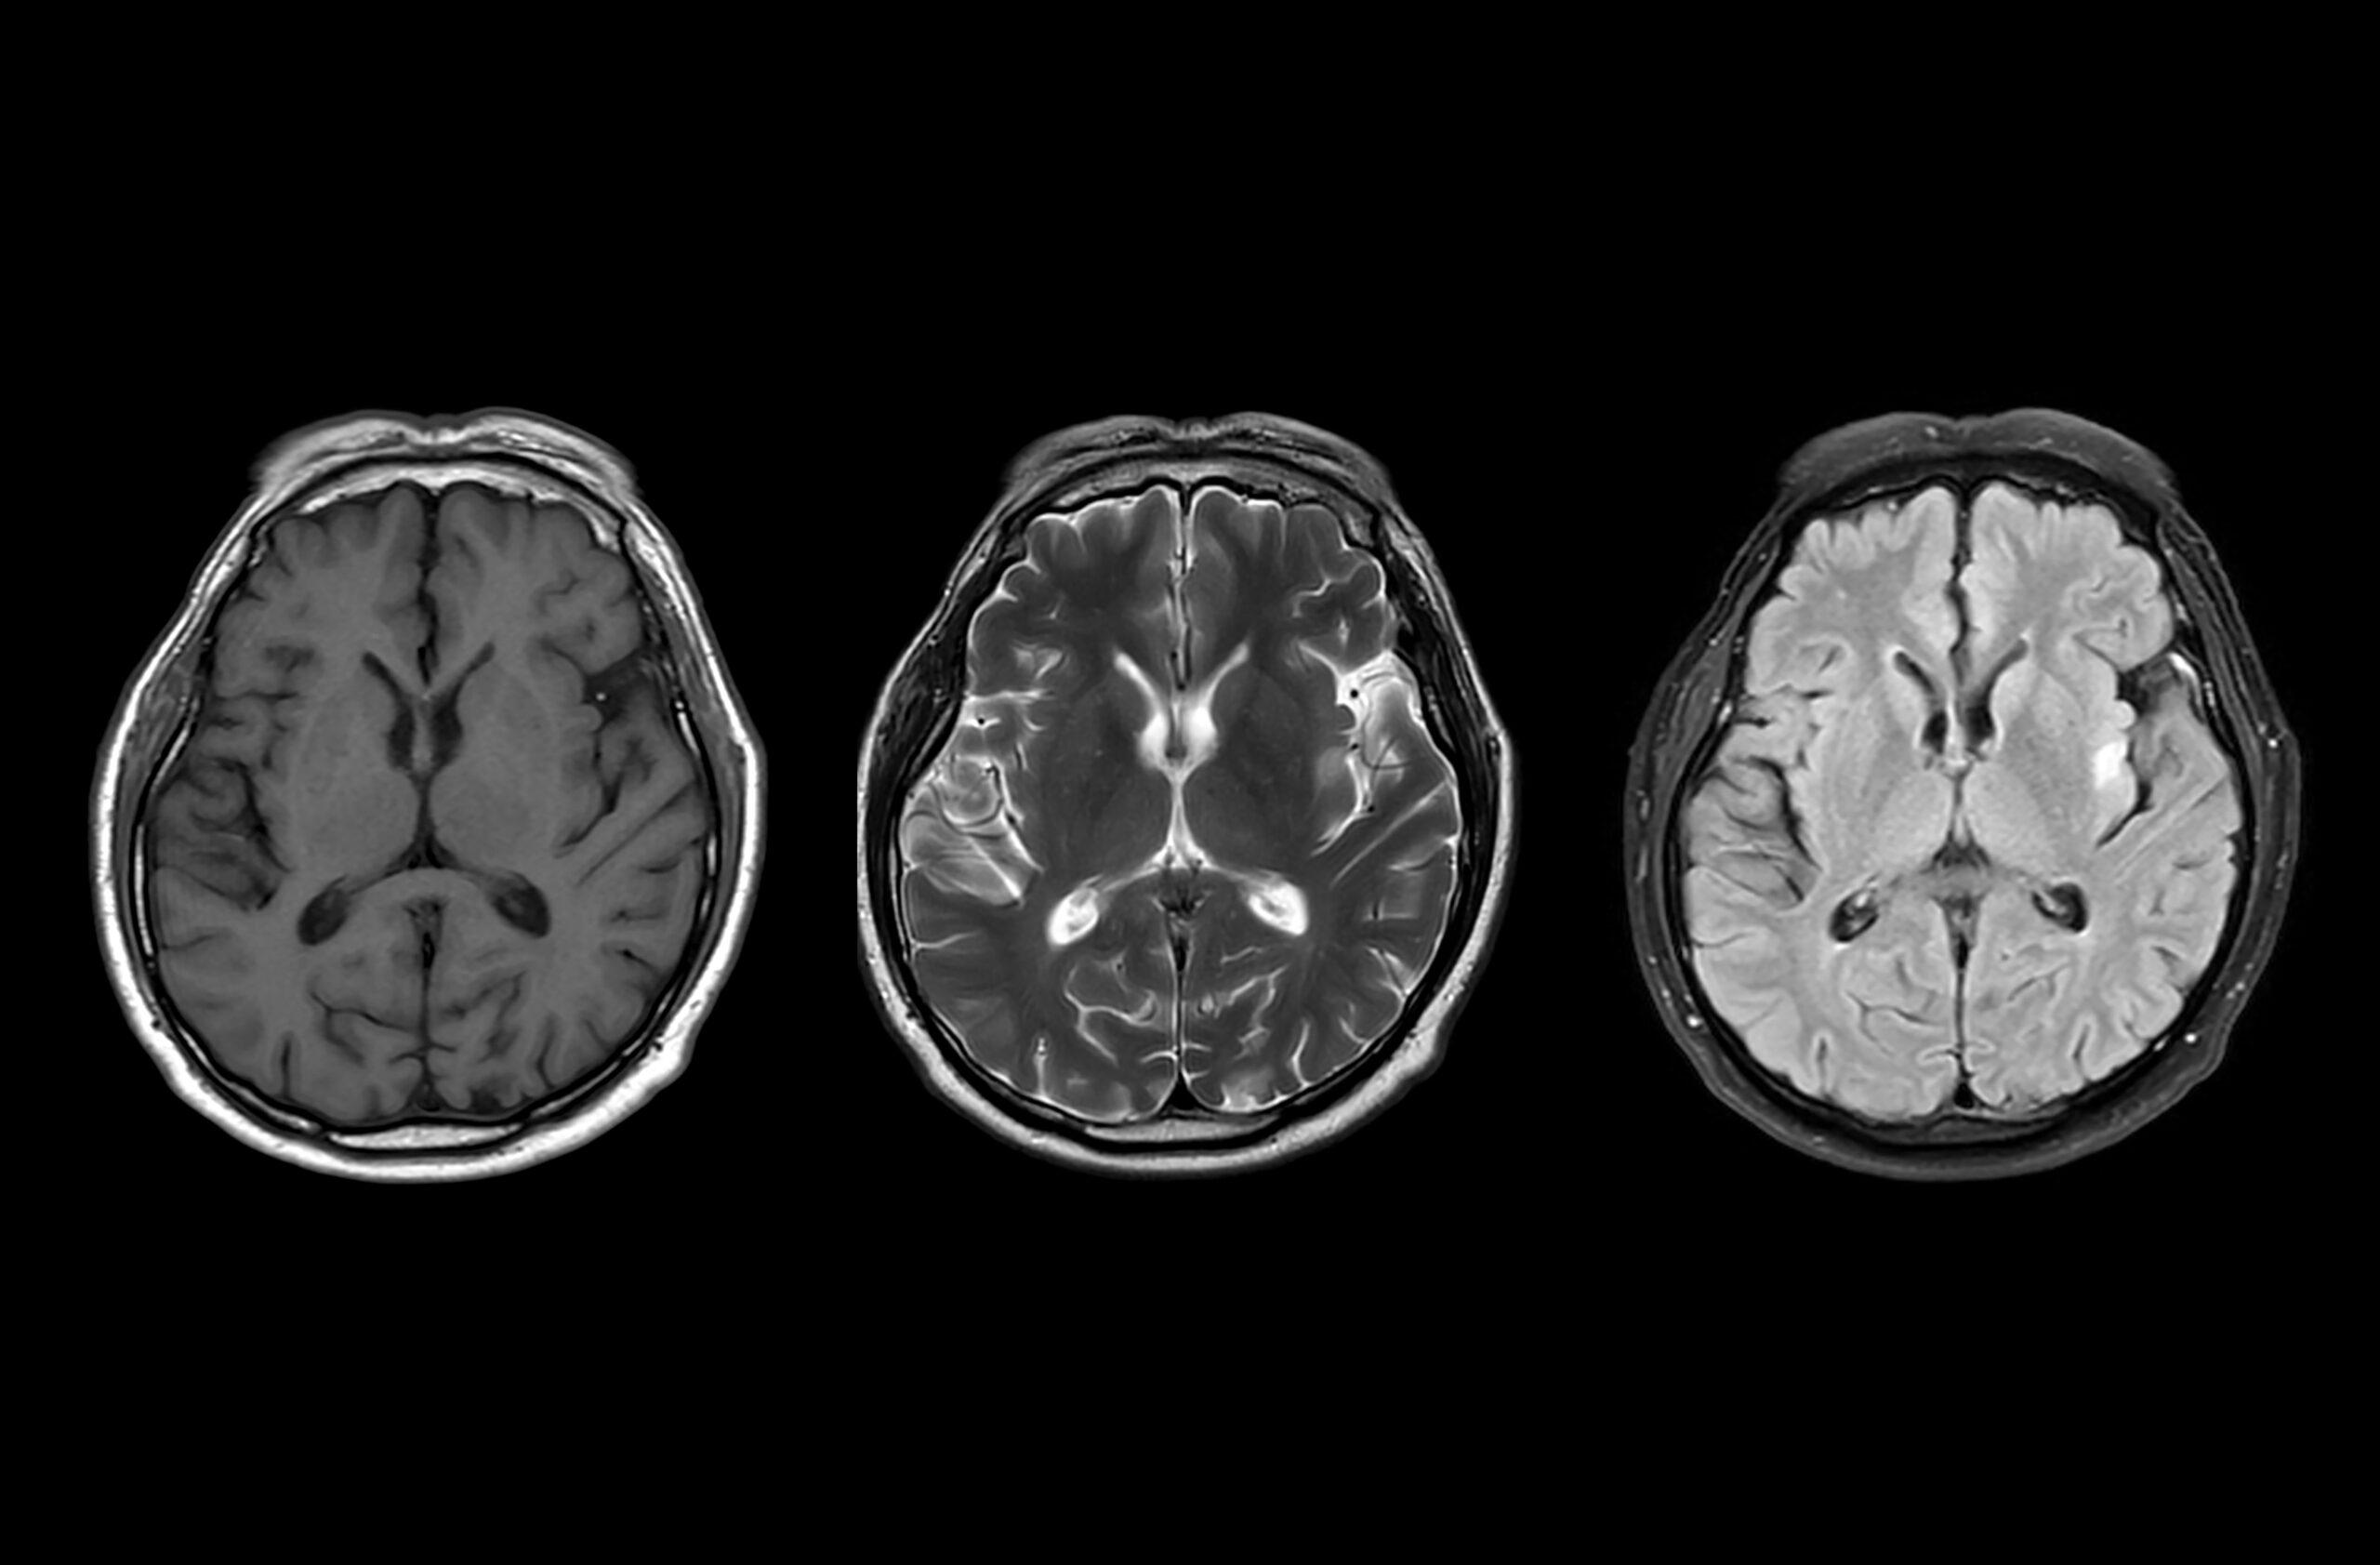

Charles Piller: OK, I’m going to wind us back all the way back to 1906, just briefly, which was the date of the kind of quote, unquote discovery of the disease by [Alois] Alzheimer, a German scientist, namesake of the disease. And he was a pathologist and a clinician, so he was treating a patient who had dementia, and this person ultimately died. And he did an autopsy on her brain, and he saw in the brain copious amounts of amyloid plaques—and this amyloid is a type of protein, and the sticky plaques are the sort of characteristic description of what scientists see as characteristic of this disease—and also another protein that’s called “tau” that tangles within nerve cells. So you have the plaques outside of the nerve cells—and also, it would be later learned that other forms of amyloid protein, soluble forms of the protein, were floating around in the fluid that bathes the brain—and also these tangles.

And so in the early ’90s, this was conceptualized into something called the “amyloid cascade hypothesis” by certain scientists. And, essentially, it’s very simple. It works this way: Amyloid plaques and other forms of amyloid protein start a cascade of biochemical effects in the brain that eventually leads to dementia.